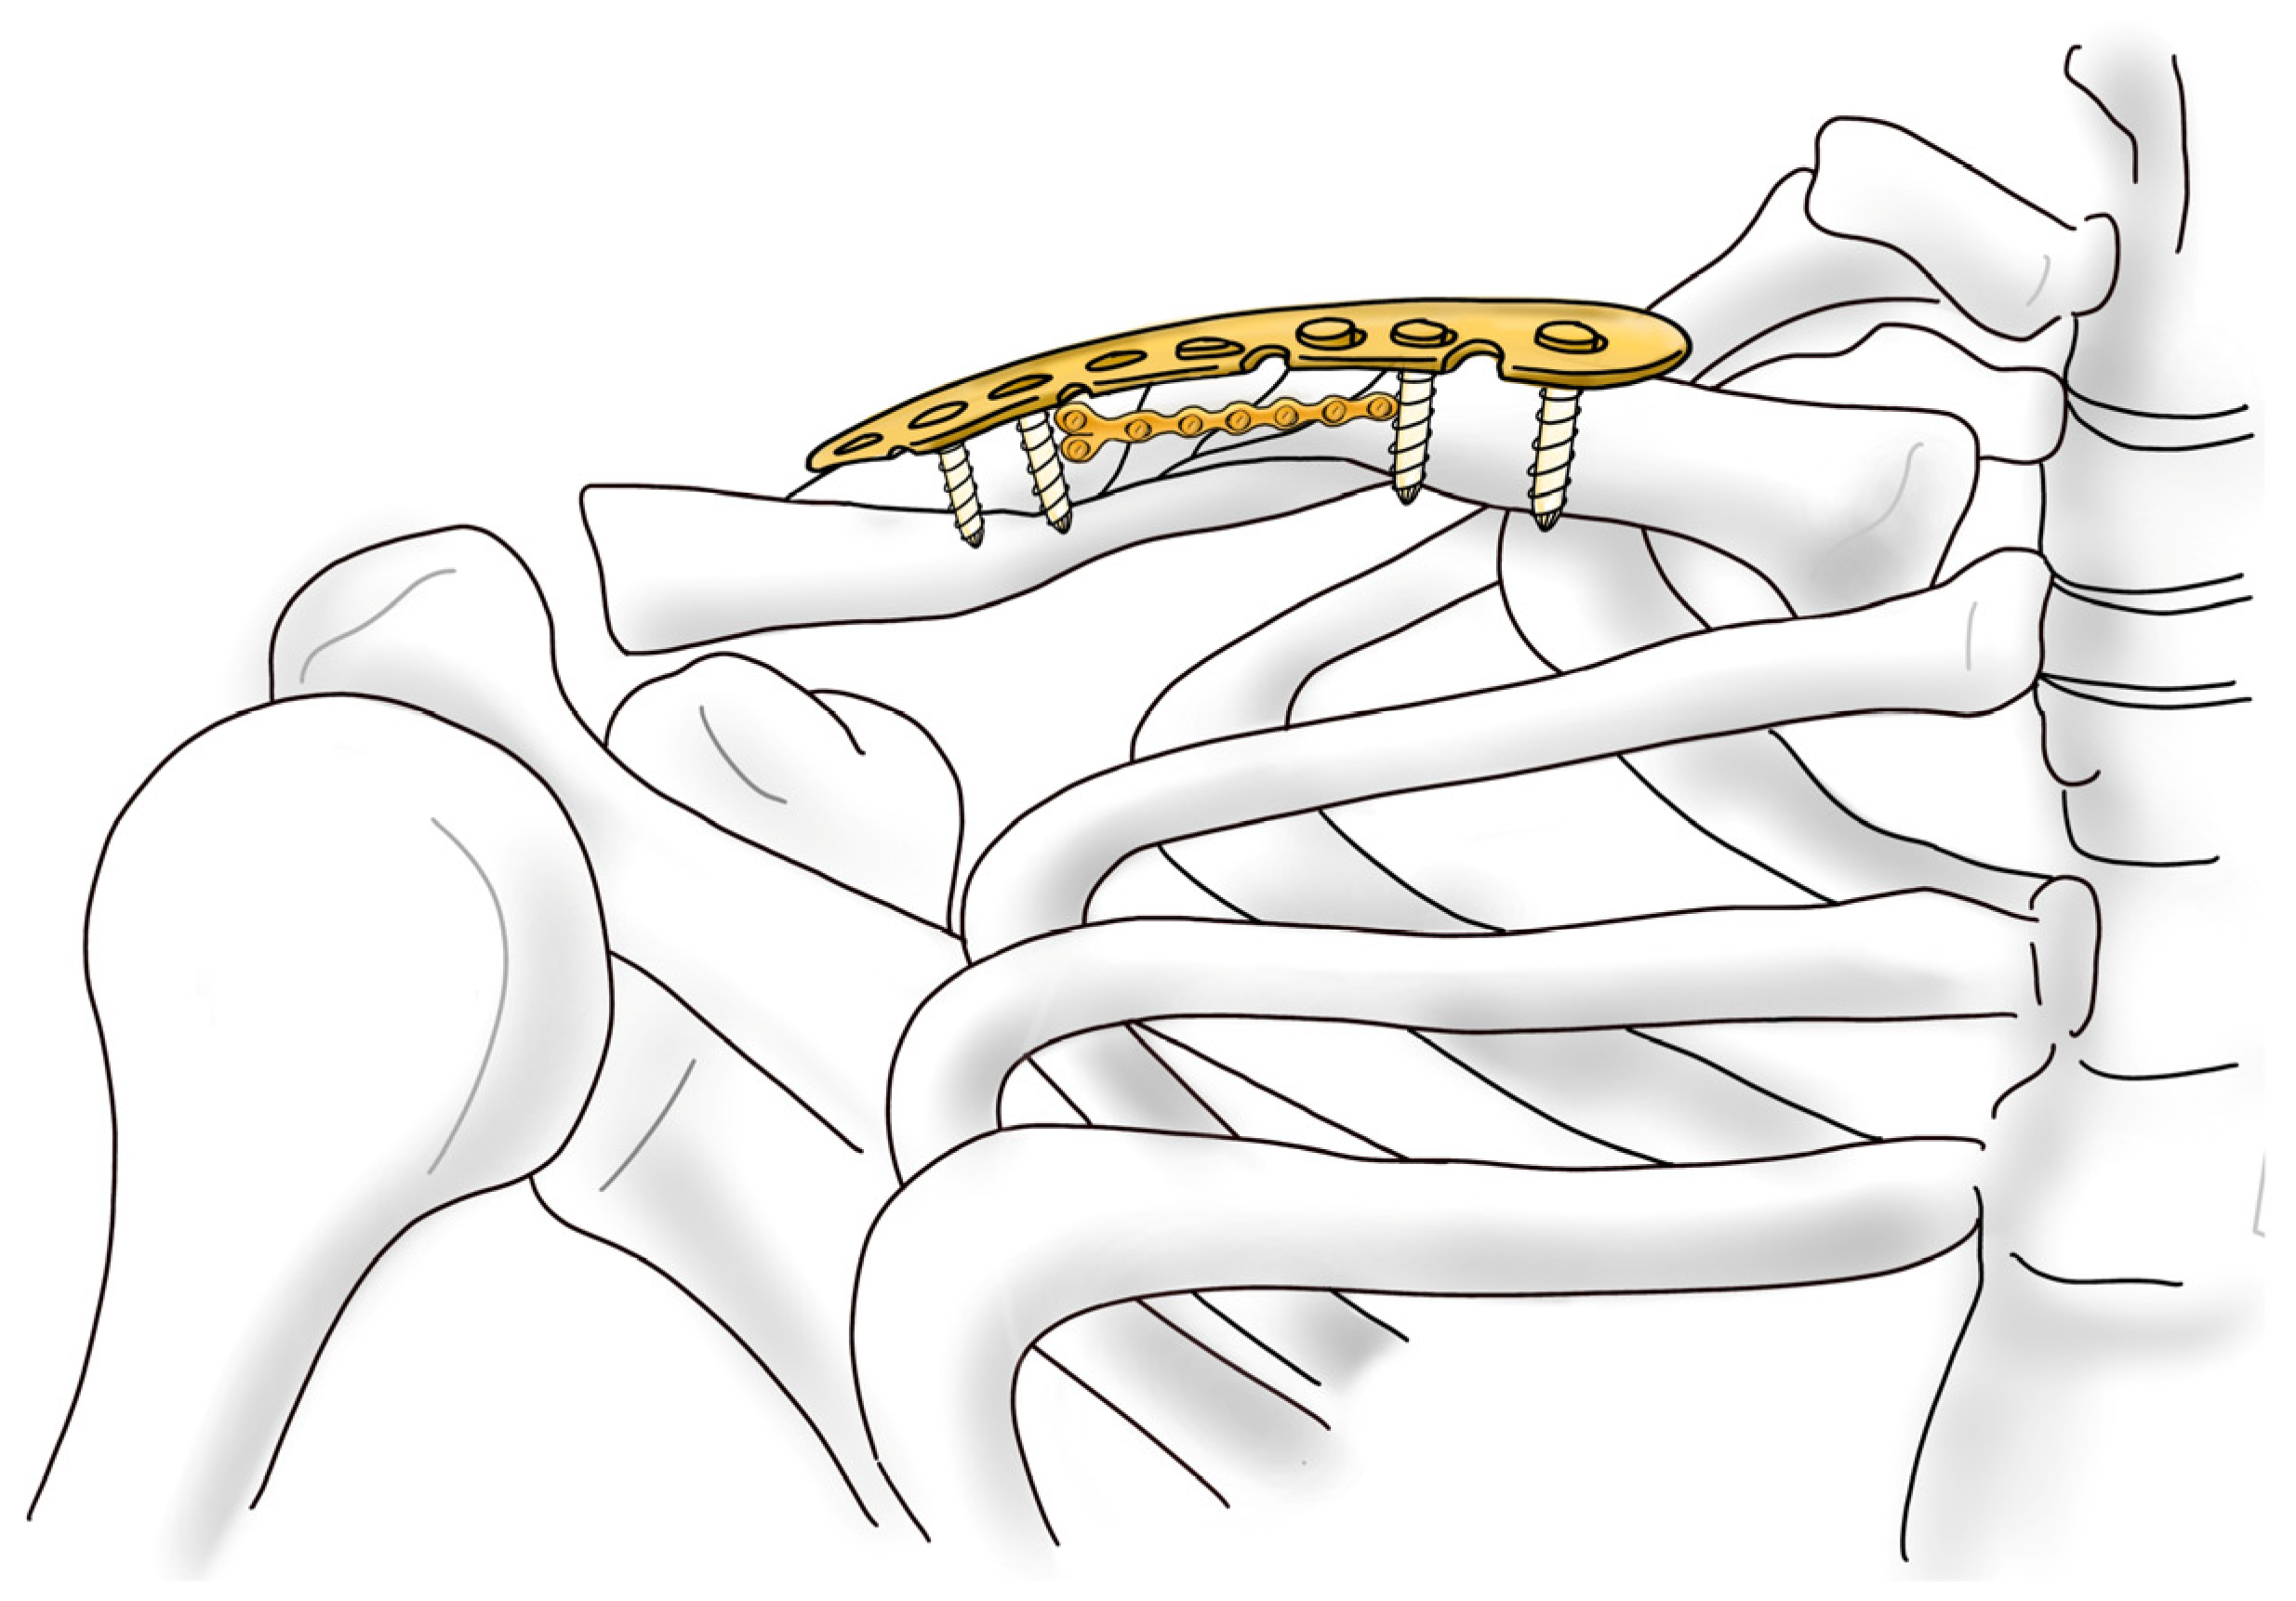

Intuitive and Minimally Invasive Surgical Technique for Comminuted Mid-Shaft Clavicle Fractures: Fixation with an Anterior Mini Plate and Superior Locking Compression Plate

2.2. Surgical Protocol